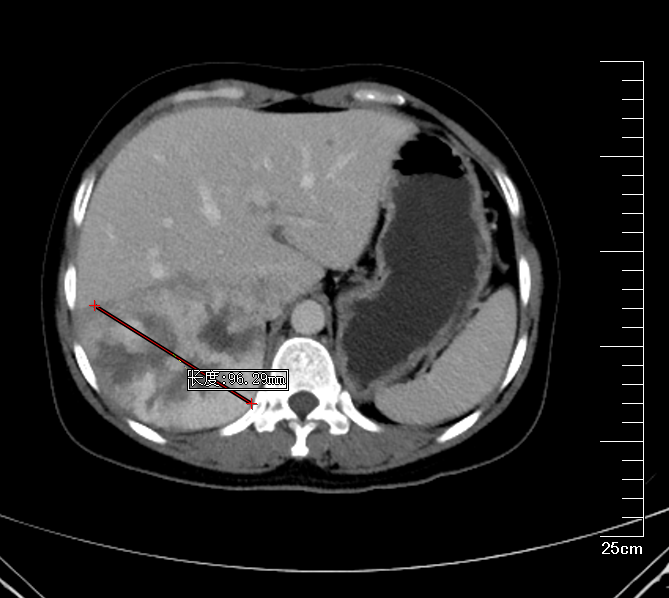

肝胆胰外科古松钢副主任在查看患者及外院CT报告后,认为患者右肝巨大肿物,大小约9*10*9.5cm,考虑为肝右后叶巨大血管瘤,需积极行手术治疗,否则血管瘤有破裂出血可能。将钱女士收治入院后,进一步完善腹部增强CT,评估患者肝储备功能以及心肺功能。

肝右叶巨大血管瘤MRI